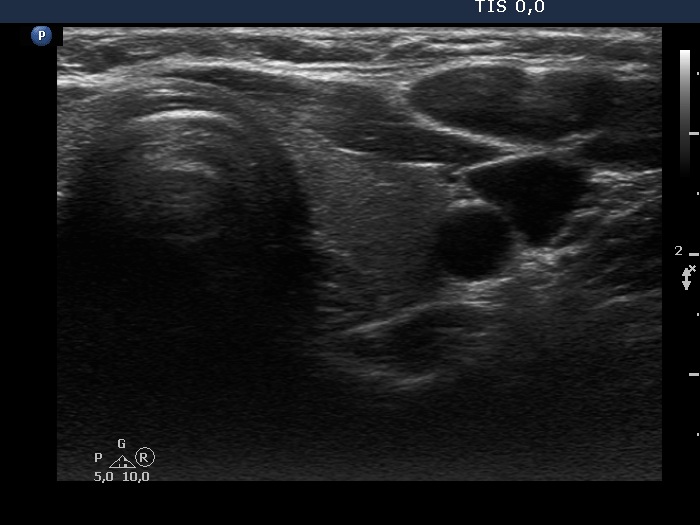

Study on 100 consecutive patients with thyroid nodule - case 051 (ultrasonographic picture 6)

Left lobe, transverse view. This lobe is intact and decreased in size.